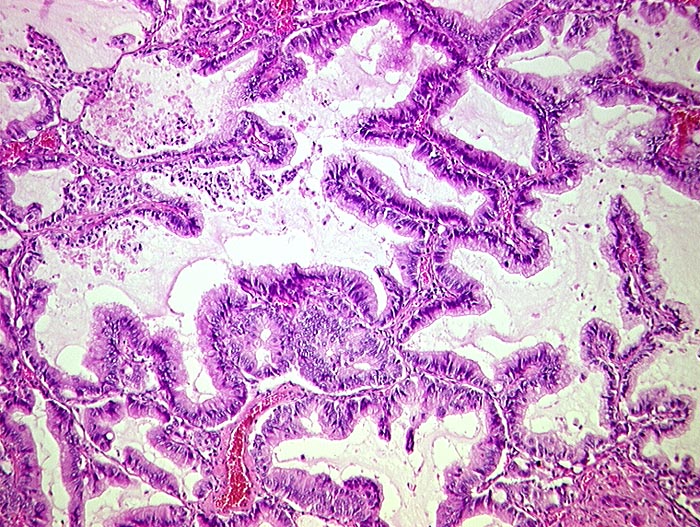

muzinöses Bronchioloalveoläres Karzinom

Hochzylindrische schleimbildende Zellen mit geringen Atypien tapezieren die Alveolarsepten aus. Das Lungengerüst bleibt erhalten.

3cm grosser peripherer Lungentumor. Metastasen Lymphknoten,Hirn, Nebennieren.